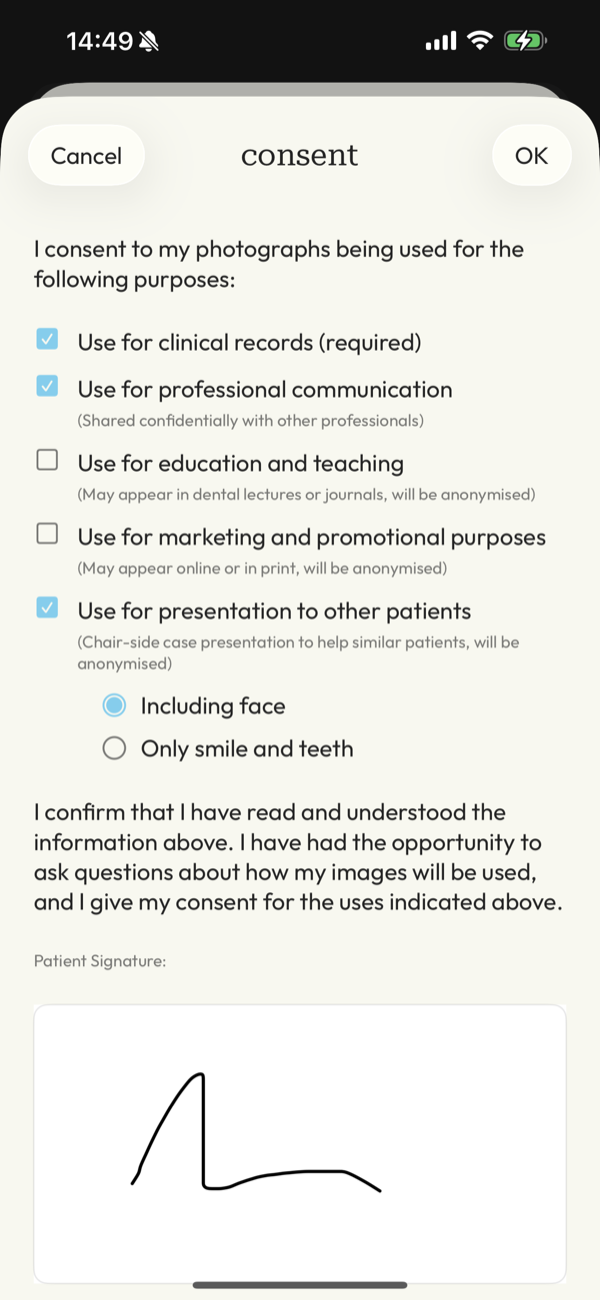

compliance worries

Managing patient consent for GDPR/HIPAA along with compliant storage and delivery can be a nightmare.

A system that puts clients at ease and you mind at rest, knowing you have the right consent and images are safe and secure.

What about consent and GDPR?

Handled as part of the workflow.

DentalFolio supports structured consent recording, allowing documentation of how images are intended to be used, such as for clinical records or education. A clear audit trail is maintained if needed.

Responsibility remains with the clinician. The app supports good practice but does not replace professional judgement.